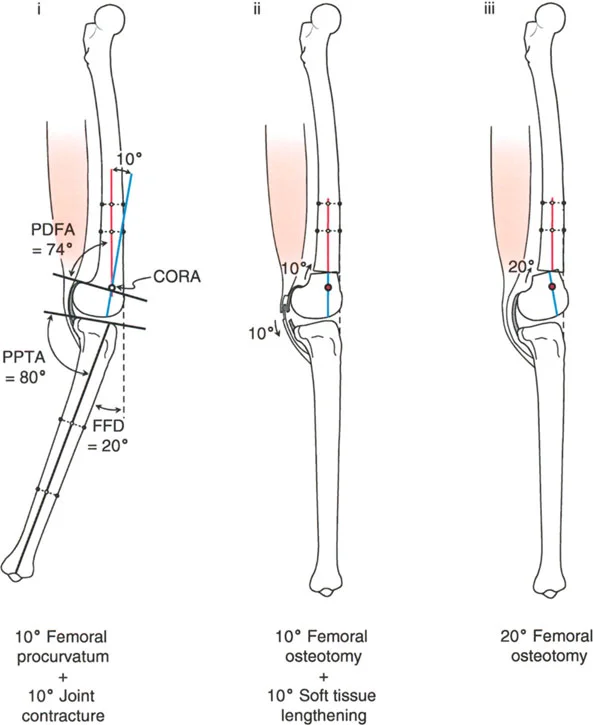

تصحيح تحدد حركة الركبة (Flexion Deformity - FFD)

تحدُّد حركة الركبة هو عدم القدرة على مد الركبة بالكامل. يمكن أن يكون سببه عظميًا أو ناتجًا عن تقلص في الأنسجة الرخوة.

- التشخيص الدقيق: يجب تحديد ما إذا كان تحدد الحركة ناتجًا عن تشوه عظمي (تقوس أمامي في الفخذ أو الساق) أو تقلص في الأنسجة الرخوة (الأوتار الخلفية، محفظة المفصل).

- قطع العظم التمديدي (Extension Osteotomy):

- إذا كان التشوه عظميًا، يتم إجراء قطع عظم تمديدي في عظم الفخذ أو الساق لتصحيح التقوس.

- الأستاذ الدكتور محمد هطيف يؤكد على أهمية عدم تصحيح الساق بأكثر من 90 درجة PPTA لتجنب فقدان الميل الخلفي الطبيعي للساق.

- تحرير الأنسجة الرخوة (Soft Tissue Release):

- إذا كان السبب هو تقلص الأنسجة الرخوة، فقد يتم إجراء إطالة للأوتار أو تحرير لمحفظة المفصل.

- إزالة النتوءات العظمية (Osteophyte Resection):

- إذا كانت النتوءات العظمية الأمامية تمنع المد الكامل، يمكن إزالتها جراحيًا.

- التصحيح التدريجي: في حالات تحدد الحركة الشديدة أو المعقدة، قد يكون التصحيح التدريجي باستخدام التثبيت الخارجي هو الخيار الأكثر أمانًا.